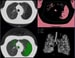

Watto: It's the post-bronchodilator FEV1 to FEV ratio< 0.7, and we're still using that for older adults. You might slightly overdiagnose COPD, but you have to look for the clinical history and the symptoms to make the diagnosis. When we're thinking about how to treat these patients, you need to know which classification they fall into. We used to use spirometry and go by the FEV1 but that was actually really poor in predicting the symptoms people would have or whether they would have an exacerbation. So, we have the modified Medical Research Council (mMRC) scale. It's a kind of grade. You decide which grade the patient fits into or you can give them the eight-question COPD Assessment Test (CAT) score.

Based on that, you can determine severity — either low- or high-severity symptoms. You also figure out whether they've had an exacerbation (eg, needed to be treated with antibiotics or steroids) or if they've been hospitalized for COPD. Patients who have been hospitalized or have been treated for an exacerbation are automatically in the E group, which is the exacerbation group. Those patients should jump right to a combination therapy when you're treating them. Paul, which medications are we really pushing in COPD now? Is it the inhaled steroids?